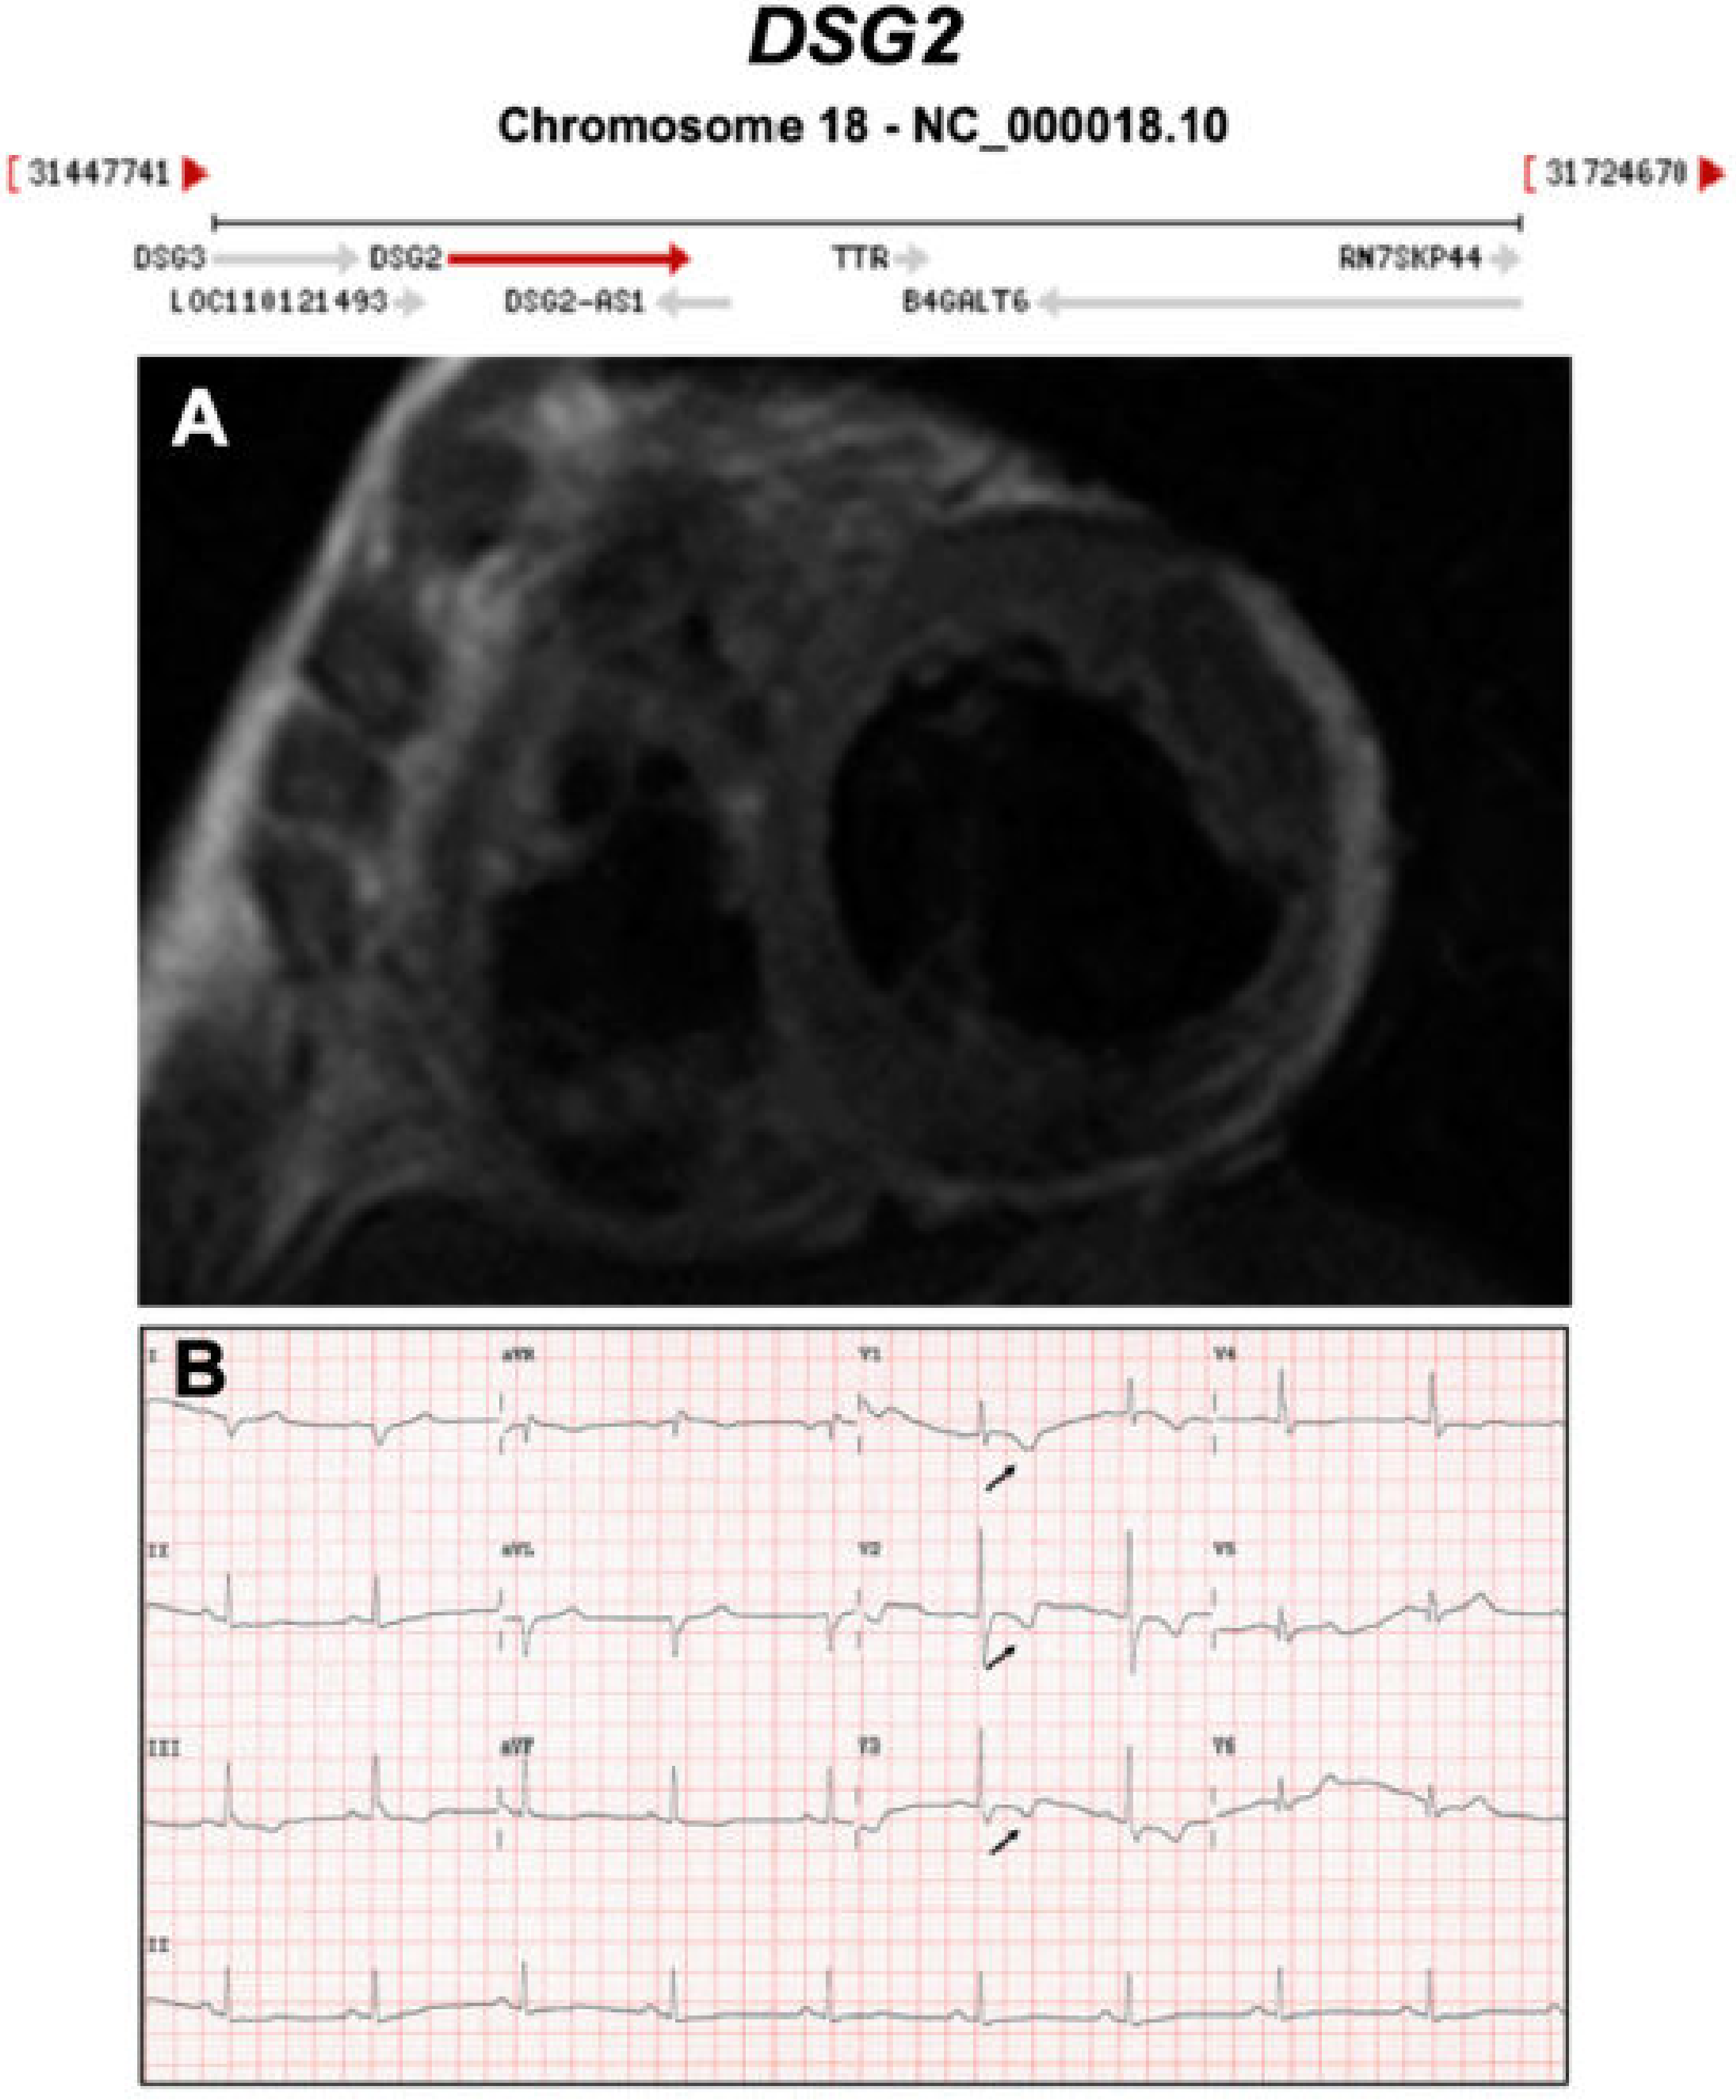

Figure 5.

Exemplar MRI and ECG finding found in ACM patients with DSG2 mutations. (A) CMR of a patient with DSG2 p.Leu237Ter mutation showing dilation of both ventricles; (B) a representative ECG of the same patient showing T wave inversion in V1-V3. Reproduced with permission from Chen et al. (2020) [35].